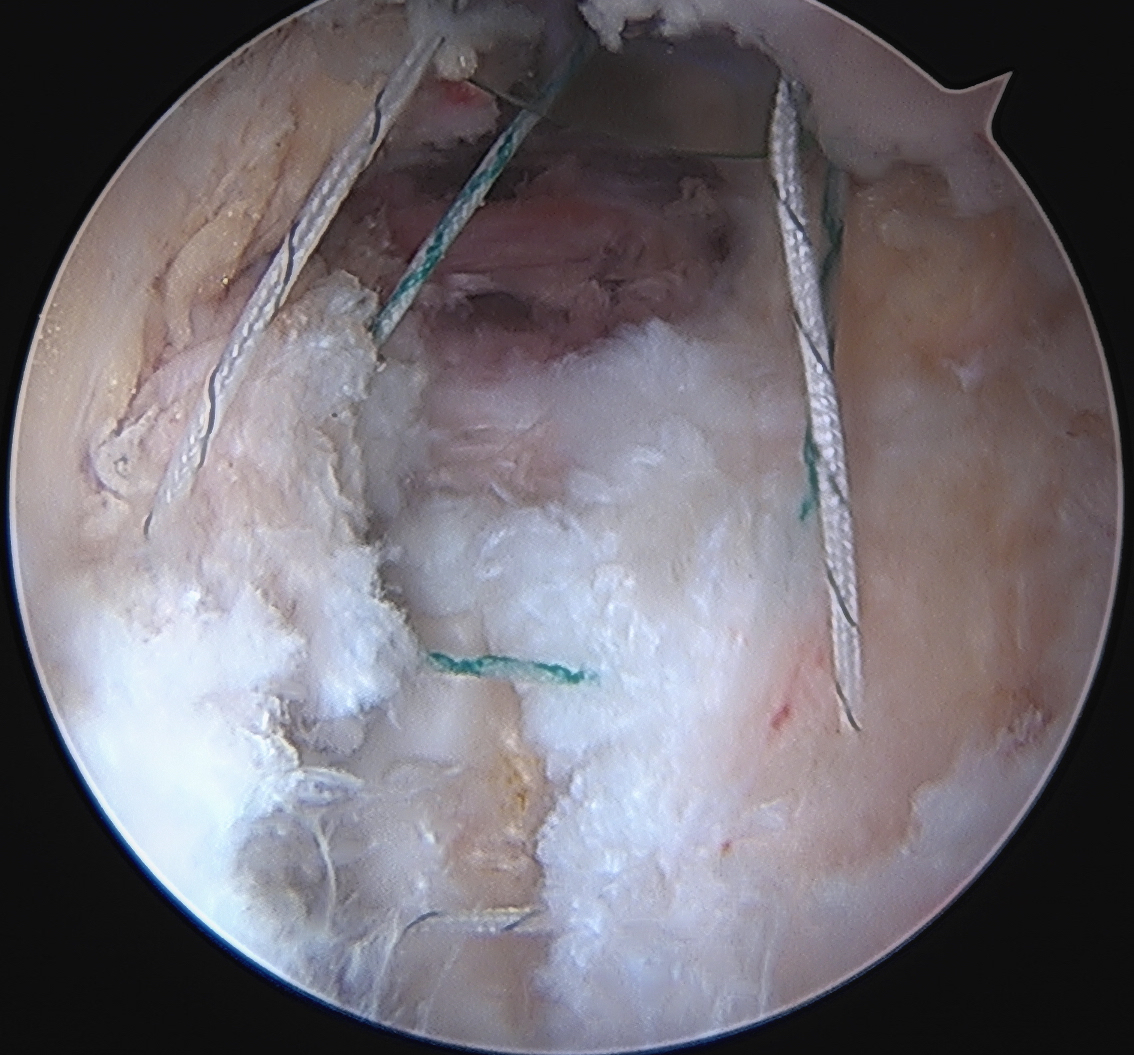

Capsular Repair

T capsule closure

Interportal capsule closure